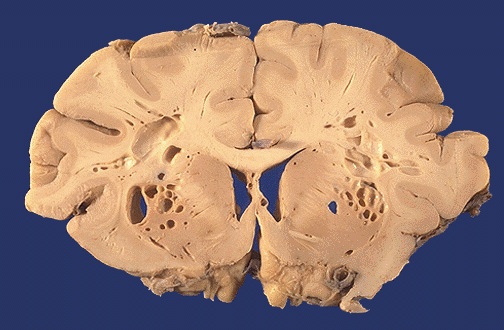

This is a postmortem artefact known as "Swiss cheese brain" in which the postmortem growth of gas forming bacteria such as Clostridium perfringens create the holes.